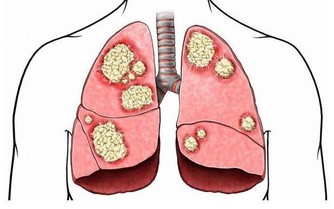

腸子能排除病原菌,合成我們生存所必要的維生素類,製造免疫力,

將製造幸福激素血清素和多巴胺的前驅物質運送至腦部等,在人類的生存上扮演著重要的角色。